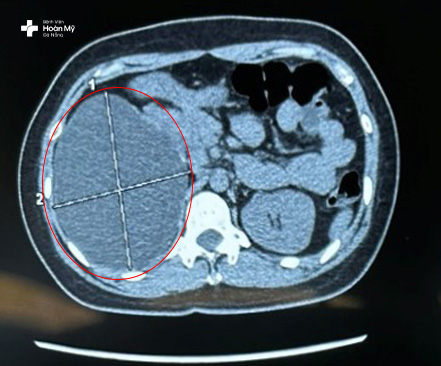

Chị T sau đó đến thăm khám tại Bệnh viện Hoàn Mỹ Đà Nẵng và được chỉ định thực hiện chụp cắt lớp hệ tiết niệu để đánh giá toàn trạng cấu trúc, tính chất nang thận, loại trừ phân biệt với u thận, thận ứ nước cục bộ trước khi đưa ra hướng điều trị phù hợp.

Hình ảnh nang thận lớn quan sát rõ trên hình chụp cắt lớp CT

“Kết quả cận lâm sàng cho thấy người bệnh có nang phải kích thước 120x101mm, nang lớn, nằm ở vị trí cực trên, chèn ép mô thận gây đau. Nang thận chèn ép lâu ngày có thể gây ảnh hưởng đến chức năng thận, cắt bỏ nang thận bằng phẫu thuật nội soi là phương pháp điều trị an toàn và hiệu quả nhất cho người bệnh lúc này” - Bác sĩ Bùi Quốc Triệu – Trưởng khoa Ngoại Tiết Niệu – Nam khoa nói.